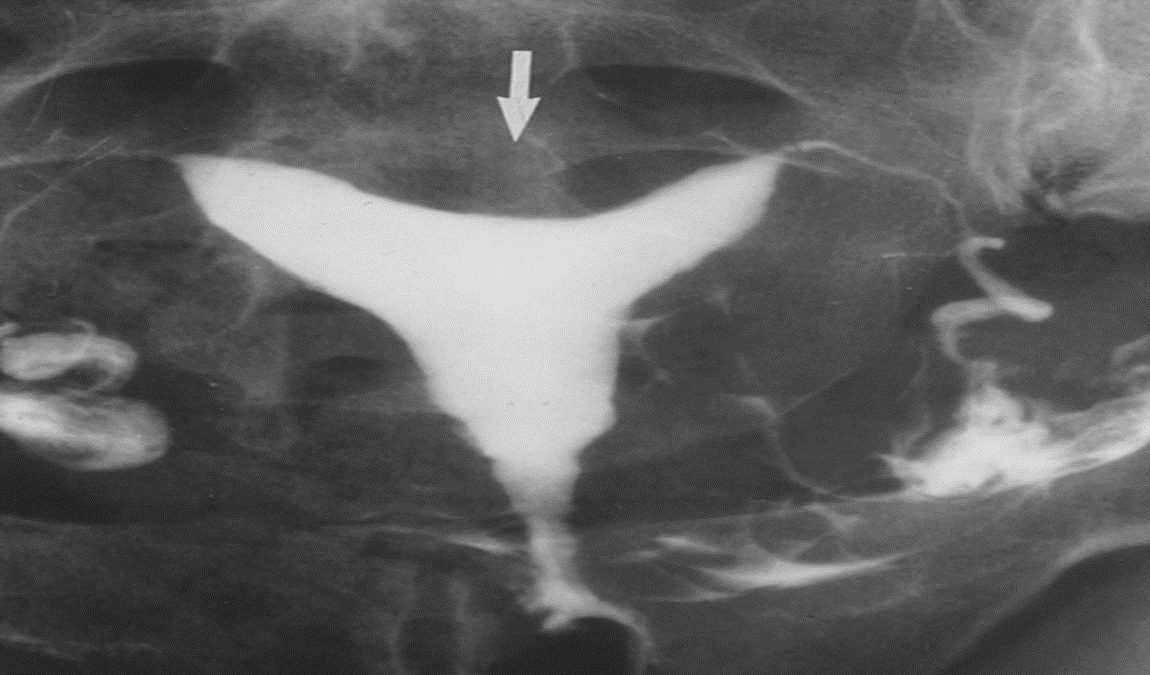

characterized by a mild indentation of the endometrium at the uterine fundus.

Hysterosalpingogram:

there is opacification of the endometrial cavity demonstrates a single uterine canal with a broad saddle-shaped smooth indentation of the uterine fundus ( usually considered to be <1 cm) and increased transverse diameter of uterine cavity